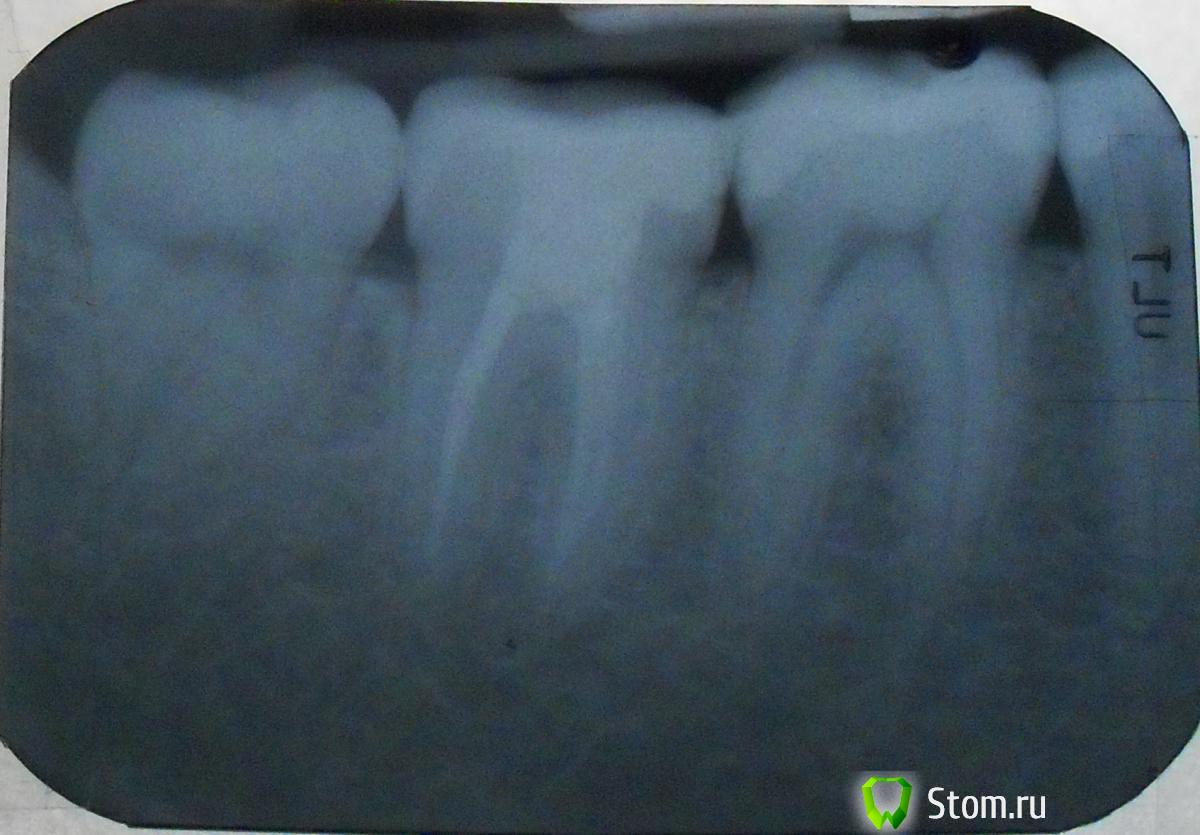

DokDent Опубликовано 24 декабря, 2011 Поделиться Опубликовано 24 декабря, 2011 Здравствуйте,Спасибо за оперативный ответ!1. Температуры нет, отека тоже.2. Зуб не болит при постукивании по нему. Но при надавливании через полминуты после надавливания начинает сильно болеть.3. Доктор запломбировал два канала, по-моему. (схема и выписка из медкарты на английском прилагается).4. В верхней челюсти тоже были сделаны пломбы, но не глубокие. Но, по моим ощущениям, боль идет снизу.5. У невропатолога не был. Стоит сходить? Вы думаете, это может быть дело не в зубе? А в чем тогда? Вы пишете,что боль сначала отдавала в пазуху-возможно,что есть воспаление нерва в каком-то из верхних зубов.Не 2,а 3 канала доктор запломбировал точно (судя по снимку),но вот есть подозрение на 4-й.А как насчёт ночных болей?И что Вы подразумеваете под надавливанием?Боль при смыкании зубов?Или появляется в момент размыкания?К невропатологу надо бы,чтоб исключить неврит или невралгию.Не помешал бы повторный снимок,может за 3 недели что-то и выплывет.А заодно и сверху. Ссылка на комментарий

Kaska Опубликовано 24 декабря, 2011 Автор Поделиться Опубликовано 24 декабря, 2011 Вы пишете,что боль сначала отдавала в пазуху-возможно,что есть воспаление нерва в каком-то из верхних зубов.Не 2,а 3 канала доктор запломбировал точно (судя по снимку),но вот есть подозрение на 4-й.А как насчёт ночных болей?И что Вы подразумеваете под надавливанием?Боль при смыкании зубов?Или появляется в момент размыкания?К невропатологу надо бы,чтоб исключить неврит или невралгию.Не помешал бы повторный снимок,может за 3 недели что-то и выплывет.А заодно и сверху. Боли есть всегда, вне зависимости от времени суток, постоянные. На стенку лезу когда бывают приступы.К невропотологу только во вторник, до этого все закрыто. Ссылка на комментарий